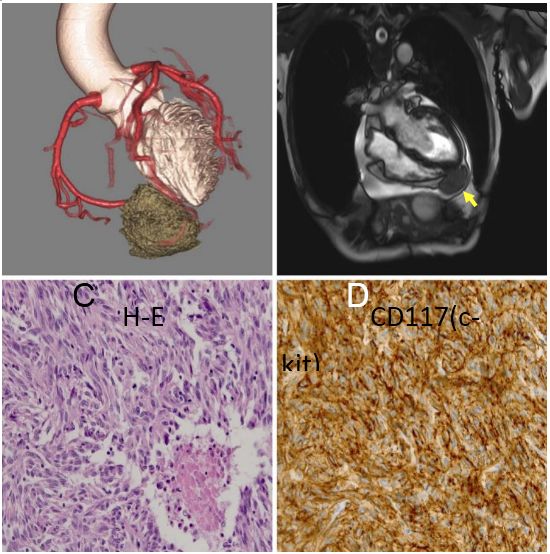

一例巨大的胃肠道间质瘤囊性病变

背景介绍:一个89岁的日本男子吐血带来我们医院。增强CT显示胃和胰腺之间的11×10×10厘米*小单大**房性囊性肿瘤(图A,箭头)。胃镜检查:发现一个大在胃体上部大弯的软凸起,凸起表明面有一个易碎的溃疡(图B)。病人入院后12天接受胃部分切除术。组织学上,被切除的标本被发现是囊性病变并有部分钙化(图片C)。囊肿包括浆液和血液,病理分析为梭形细胞成分,且c-kit和CD34免疫组化阳性(图片D)。有丝分裂率为10/50个高倍视野,根据弗莱彻的危险分级诊断为胃肠道间质瘤(1)。大多数胃肠道间质瘤为实性肿瘤,囊性改变少见(2)。这种情况下囊性改变可能是由于肿瘤的快速生长和坏死引起的。这种情况下囊性改变可能是由肿瘤的快速生长和坏死引起的。胃肠道间质瘤表现为单房性囊性病变,虽然罕见,应于上腹部囊性病变的鉴别诊断。